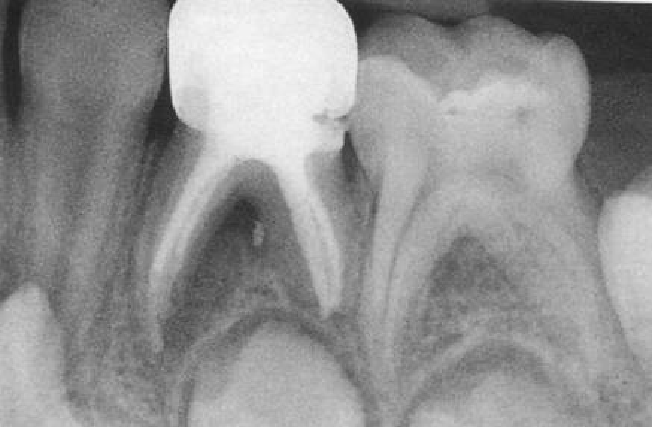

• 上颌乳磨牙大部分有3个牙根,远颊根和腭根常融合;近颊根可能有1~2个根管,远颊根和腭根都只有1个根管。

• 下颌乳磨牙的近中根常见2个根管,远中根常见1个根管,也有2个根管;近中根最常见Vertucci’s types Ⅳ类结构根管,远中根最常见Ⅰ类结构根管;少数存在5个根管。

2、vitapex

组成:氢氧化钙+碘仿+其他